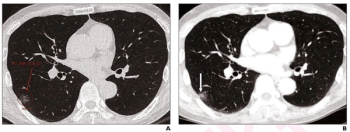

Researchers also noted a greater than 30 percent increase in treatment management changes resulting from the use of CT-based adjunctive AI to detect lung metastases in colorectal cancer patients.

In comparison to radiologist assessment, the use of AI to pre-screen patients with low-dose CT lung cancer screening provided a 12 percent reduction in mean interpretation time with a slight increase in specificity and a slight decrease in the recall rate, according to new research.